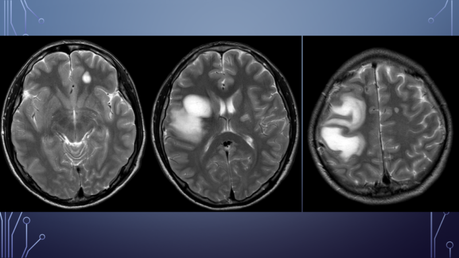

PA: Inicia hace 5 meses con amnesia, cefalea generalizada la cual empeora con el ejercicio, agregándose parálisis facial izquierda por lo que acude con neurólogo privado solicitando TC y posteriormente RM.

El paciente es diagnosticado con EM.

Inicia tratamiento con altas dosis de corticoides.

Deterioro neurológico: parálisis de miembro superior izquierdo y hemiparesia izquierda.